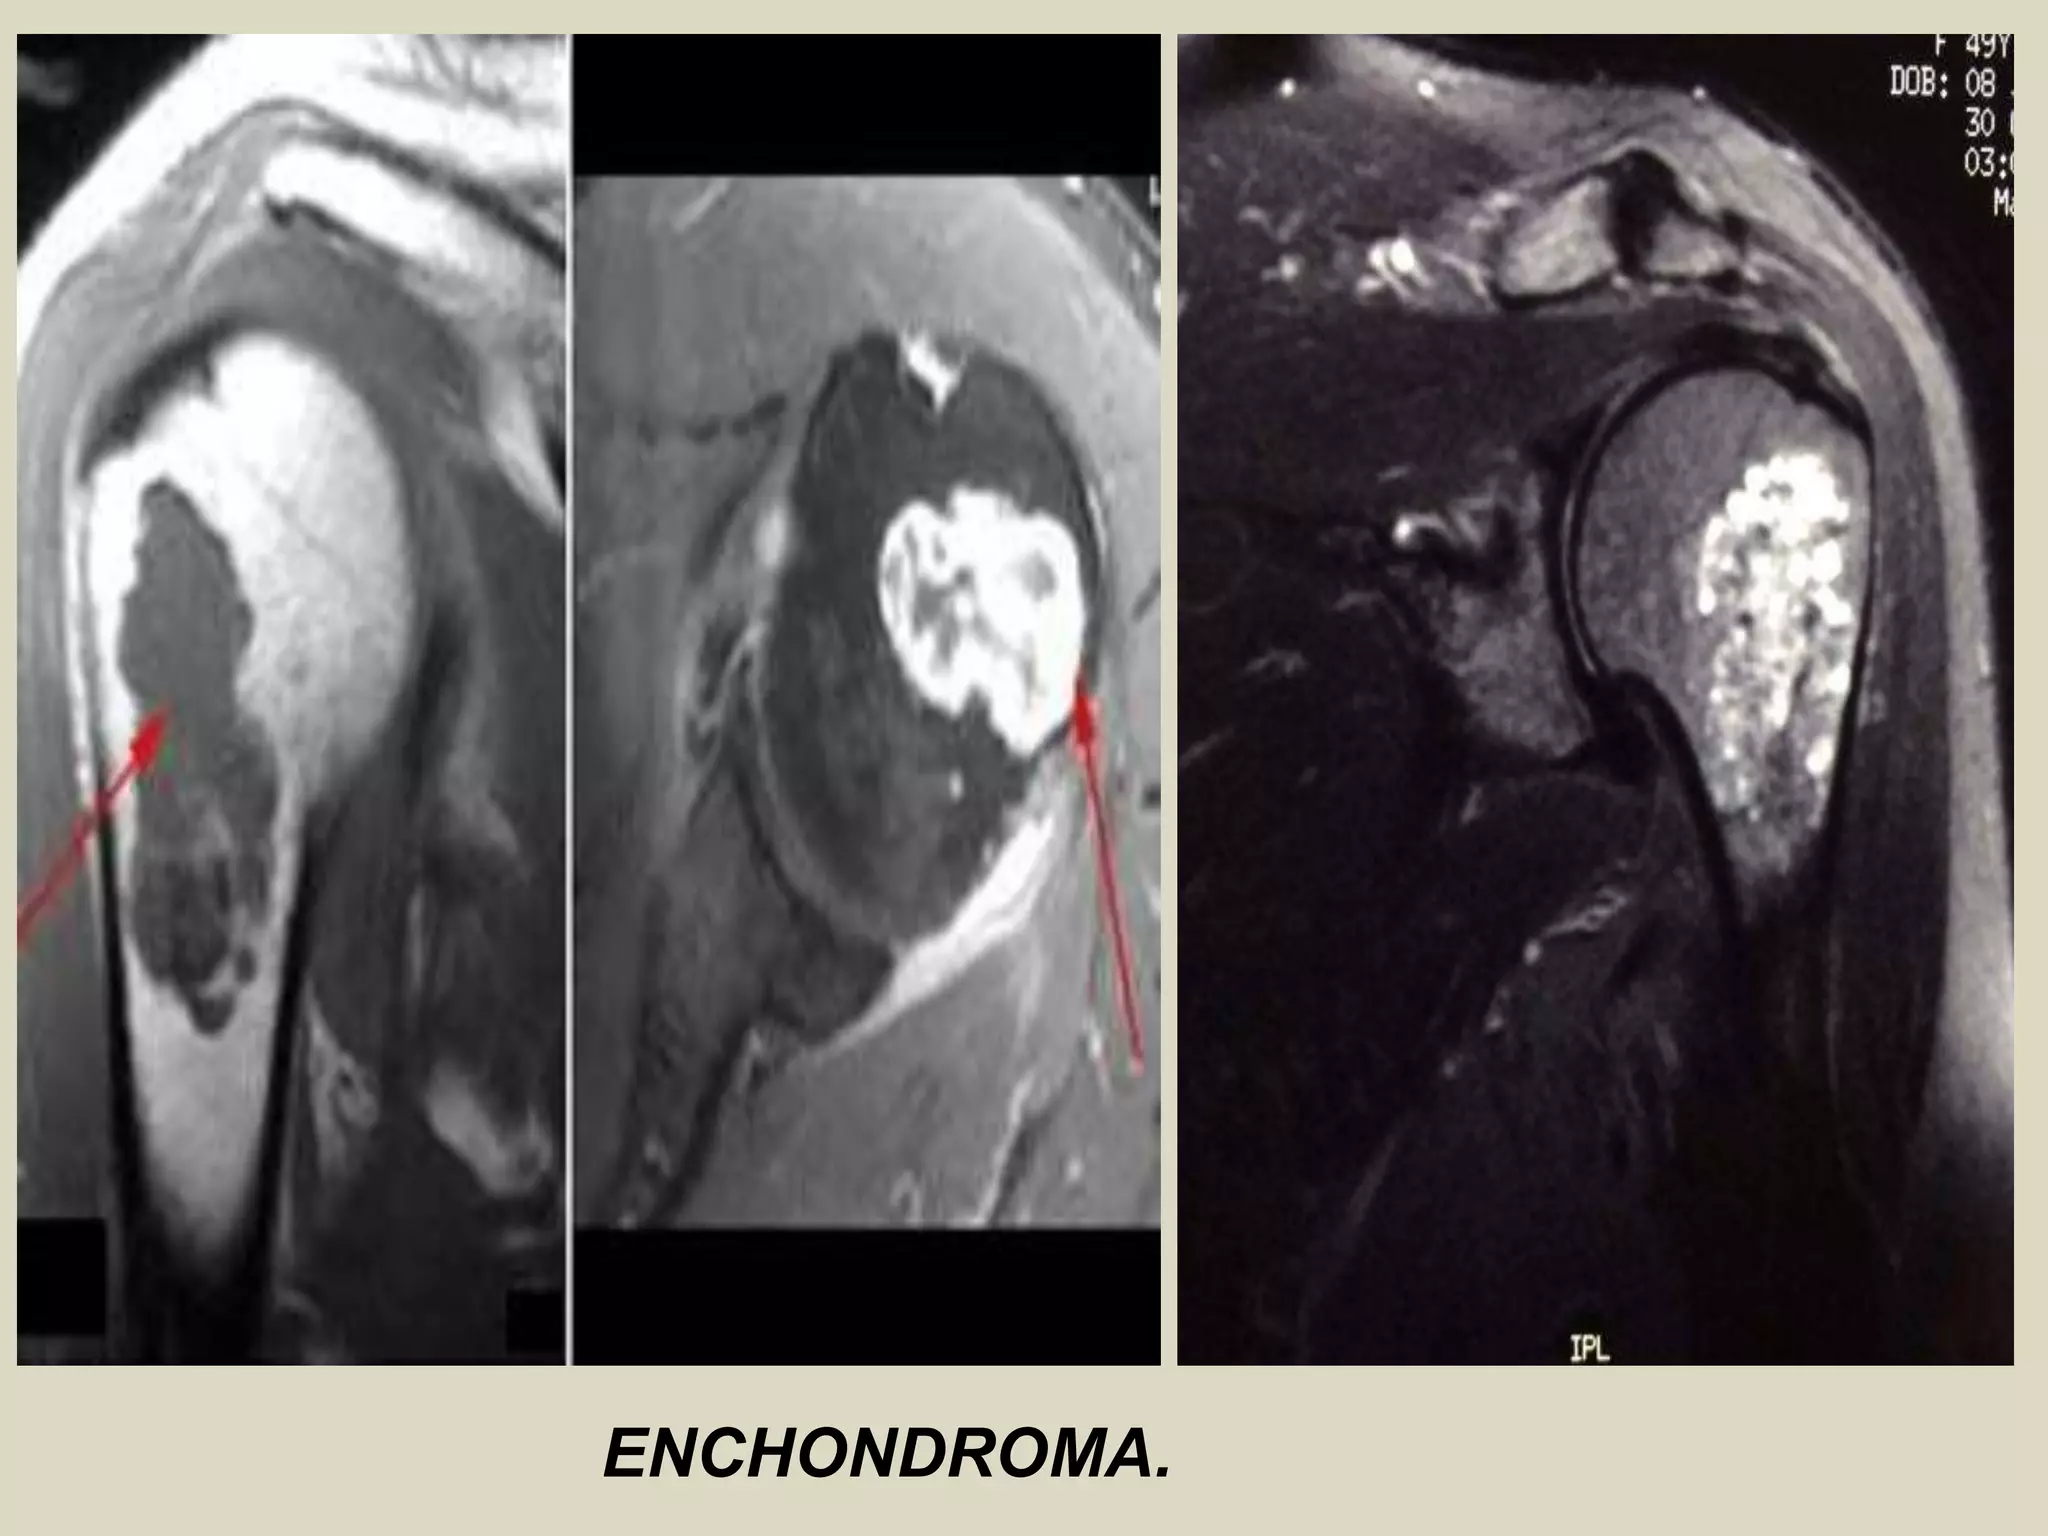

ENCHONDROMA AND ENCHONDROMATOSIS

Definition: Benign hyaline cartilage neoplasm of medullary bone.

- Enchondromatosis, is defined as two or more enchondromas, and occurs in two clinical settings: 90% are

associated with Ollier disease (two or more enchondromas) 10% are seen in Maffucci syndrome

Imaging:

- Well marginated tumors that vary from radiolucent to heavily mineralized.

- Mineralization pattern is characteristic, consisting of punctate, flocculent, or ring and arc pattern.

- Long bone tumors are usually centrally located within metaphysis.

- Diaphyseal long bone tumors are less common, and epiphyseal tumors are rare.

- Enchondromas in the small tubular bones can be centrally or eccentrically located, and larger tumors may

completely replace medullary cavity.

- More extensive endosteal erosion is considered suspicious for low grade chondrosarcoma.

- Cortical destruction and soft tissue invasion should never be seen in enchondromas and would be most

consistent with chondrosarcoma.

ENCHONDROMA

ENCHONDROMA.